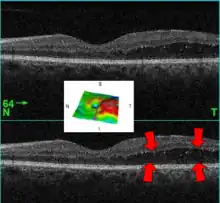

| A 61-year-old man with medical history of type 2 diabetes that presents a macular edema, evidenced by an OCT (the edema marked with arrows). The central image is a 3D reconstruction of the retinal thickness (the edema is coloured in red). | |